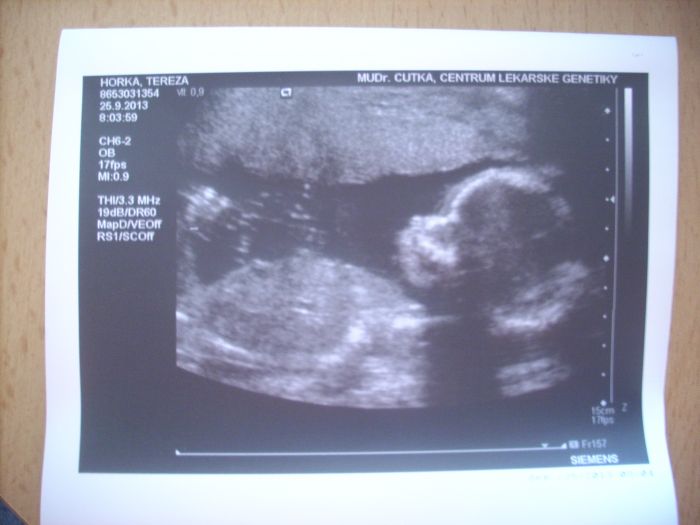

Ahoj, holky, tak máme za sebou genetiku, všechno je v pořádku, mimčo je naprosto zdravé. A takhle teď vypadáme, ve 19+6, čekáme holčičku, zatím máme 25 cm, cca 340g